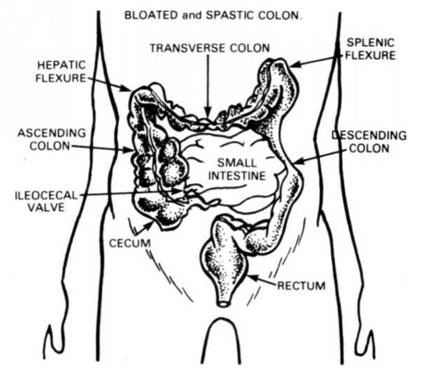

ABOVE What a person's Colon should be.

BELOW: What happens when the COLON FAILS TO RECEIVE NECESSARY COLON IRRIGATIONS.